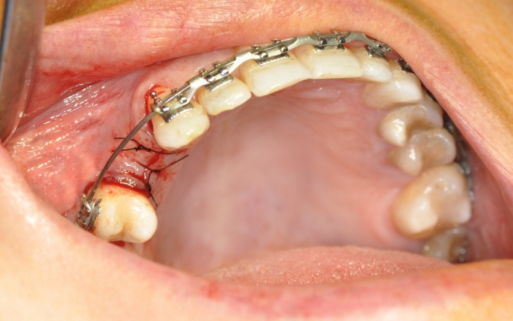

Zajmuję się zarówno wszczepianiem implantów, jak i rekonstrukcją ubytków kostnych, a także podnoszeniem dna zatoki szczękowej, co pozwala na uzyskanie optymalnych warunków do wszczepienia implantów, nawet w przypadku dużych ubytków kostnych.

Założenie jednego implantu trwa średnio 15 minut i zwykle odbywa się przy miejscowym znieczuleniu.

Ze względu na to, że wszczepienie implantu odbywa się przy znieczuleniu miejscowym, zabieg ten porównywalny jest do usunięcia zęba jednokorzeniowego.

Po jego zakończeniu stomatolog najczęściej zaleca terapię antybiotykową, która ma zapobiec infekcji.

W przypadku niedoboru tkanki kostnej najpierw wykonuje się zabieg jej odbudowy, a nastepnie zabieg implantologiczny.